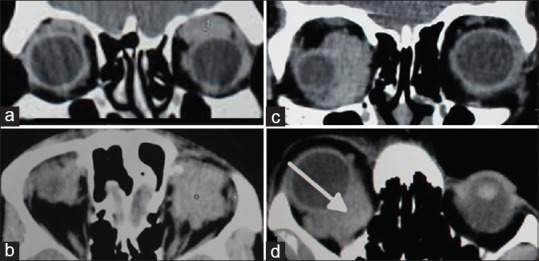

目的:旨在分析眼眶病变的放射学诊断及其与最终组织病理学结果的相关性。我们比较了外部放射科医生和内部专门从事眼眶成像的放射科医生的初步报告,以评估眼眶成像诊断的准确性:这是一项回顾性病历审查,对象是 7 年间转诊到南印度一家三级眼科医疗中心的 40 名患者。这些患者已经在其他地方做了眼眶造影。内部放射科医生重新评估了影像学检查结果。放射学检查结果与组织病理学诊断结果相互关联。比较了两位放射科医生的诊断准确性。计算了两组患者区分恶性和良性病变的敏感性、特异性、阳性预测值(PPV)和阴性预测值。分析了两组放射诊断对肿瘤性和炎症性病变的敏感性和 PPV:本院放射科医生和院外放射科医生区分恶性病变和良性病变及炎症性病变的准确率分别为 95% (κ = 0.9 [0.764, 0.997])和 50% (κ = 0.036 [-0.160, 0.232])。本院放射科医生对良性病变的放射诊断灵敏度和 PPV 分别为 93.31% 和 100%,对恶性病变的灵敏度和 PPV 分别为 95.24% 和 95.24%。相反,外部放射科医生的报告显示,良性病变的敏感性和 PPV 分别为 76.92% 和 66.67%,恶性病变的敏感性和 PPV 分别为 14.28% 和 60%:结论:如果由在眼眶成像方面经验丰富的放射科医生进行分析,放射诊断的准确性会很高。

Purpose: The objective is to analyze the radiological diagnosis of orbital lesions and their correlation with the final histopathological findings. We compared the initial reports by extramural radiologists and an in-house radiologist specialized in orbital imaging to evaluate the diagnostic accuracy in the interpretation of orbital imaging.

Methods: This was a retrospective chart review of forty patients referred to a Tertiary Eye Care Center in South India over a period of 7 years. These patients already had their imaging done elsewhere. The imaging was re-evaluated by an in-house radiologist. The radiological findings were correlated with the histopathological diagnosis. The diagnostic accuracy between the two radiologists was compared. The sensitivity, specificity, positive predictive value (PPV), and negative predictive value in differentiating malignant from benign lesions were calculated in both groups. The sensitivity and PPV of the radiological diagnosis for neoplastic and inflammatory lesions in both groups were analyzed.

Results: The accuracy in differentiating malignant from benign and inflammatory lesions by our in-house radiologist and extramural radiologists was 95% (κ = 0.9 [0.764, 0.997]) and 50% (κ = 0.036 [-0.160, 0.232]), respectively. The sensitivity and PPV of the radiological diagnosis by our in-house radiologist were 93.31% and 100% for benign lesions and 95.24% and 95.24% for malignant lesions. On the contrary, reports from the extramural radiologists showed a sensitivity and PPV of 76.92% and 66.67% for benign lesions and 14.28% and 60% for malignant lesions.

Conclusion: A high radiological diagnostic accuracy is possible when analyzed by radiologists experienced in orbital imaging.